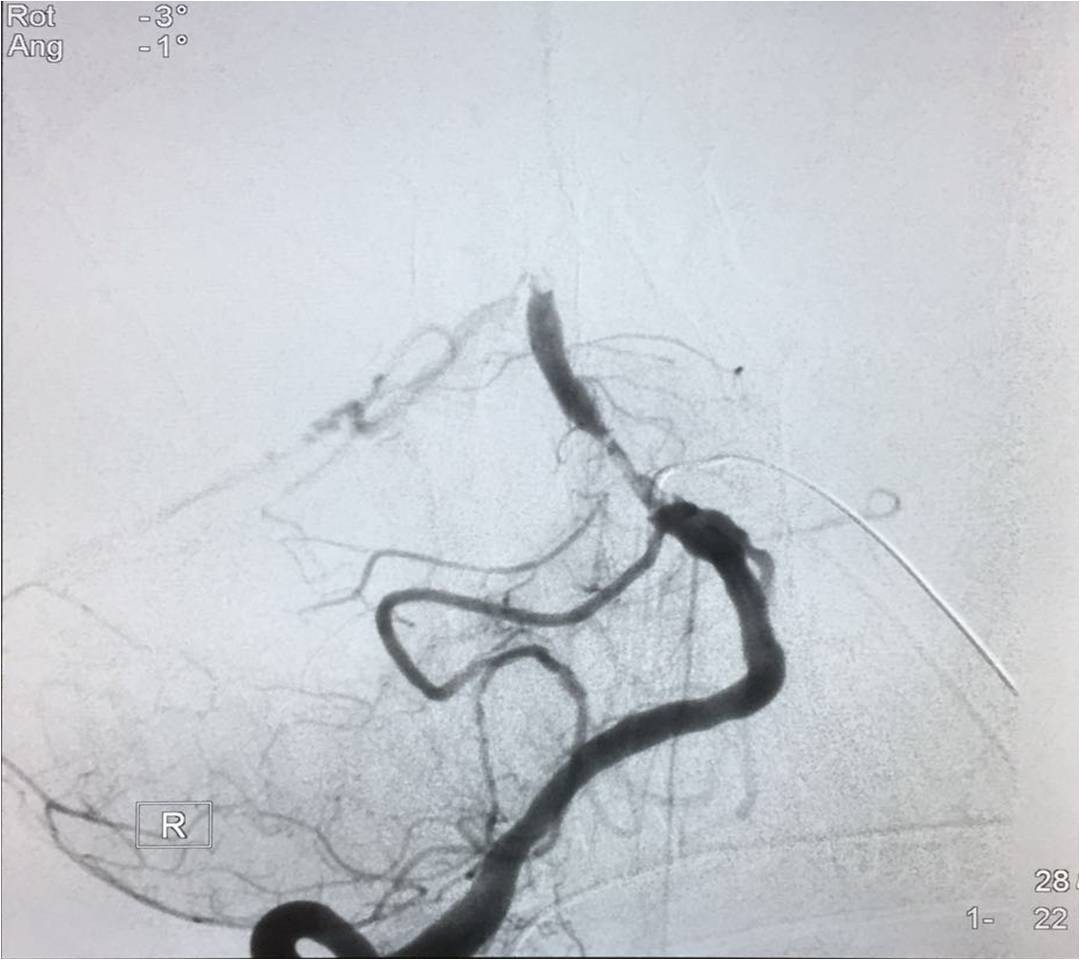

▼微导管定位